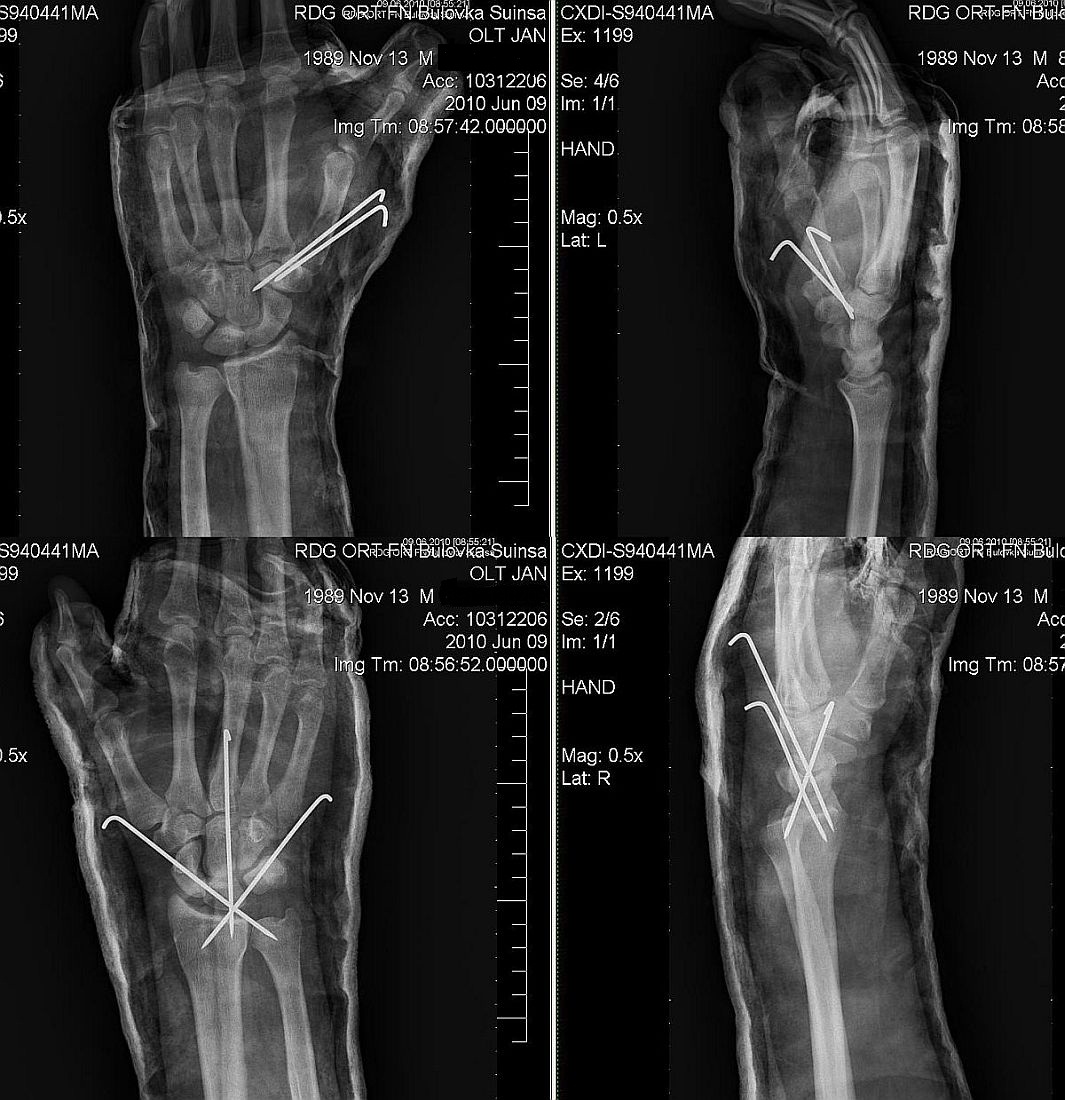

Šrouby do ruky

Praha - Česká republika - Honza Olt - by: ?